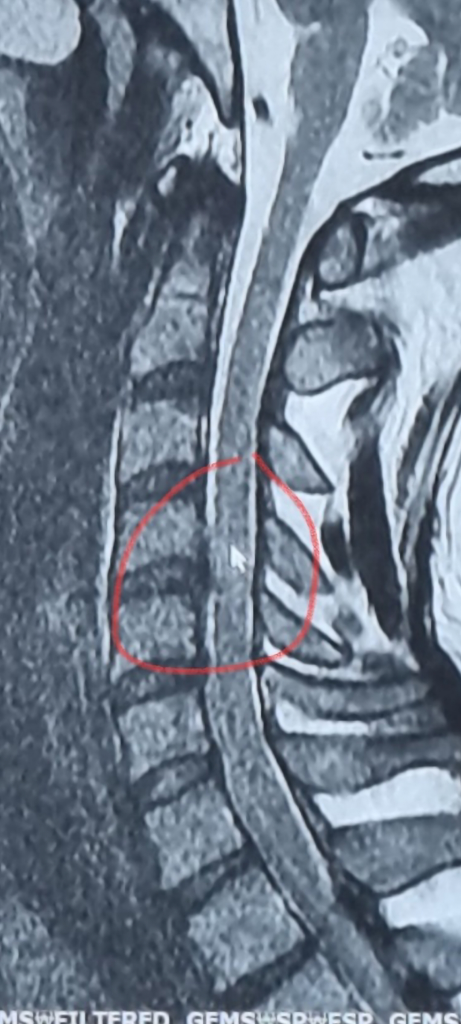

mri 사진을 보고 여태 괜찮은거같다고 판단했고 카페회원님들도 보여준 사진상으로는 괜찮아보인다 하셨는데 오늘 처음으로 다른각도의 사진을보니 조금 심각한거같아서 바로 찍었습니다 사진 첨부할테니 한번봐주세요...

3.오늘 처음 다른각도에서 본 mri 사진(신경관?을 상당히 침범) 같은날 찍은 mri 입니다

저런식으로 사진을 찍어 올린 걸로는 정확한 판독이 되지는 않으나, 올려주신 사진만으로는 탈출증이 심각하게 있어보이진 않습니다. 신경관은 세번째 사진에서 판단할수 없습니다.